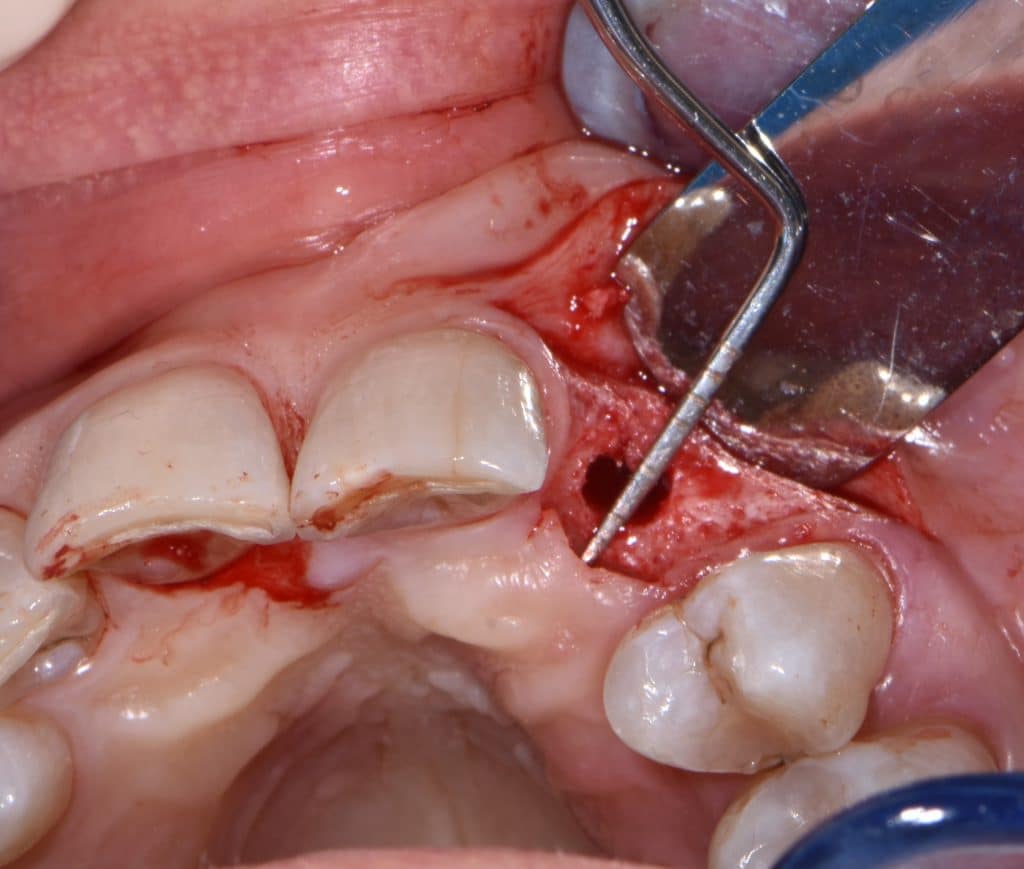

La pz N.G. di anni 52 (ASA 1) viene visitata nel mese di settembre 2017 per la mobilità ed inestetismo dell’elemento protesico 22, (foto iniziali sequenza 1) si evidenzia una frattura parziale della radice, si decide per l’estrazione ( foto sequenza 2) e sostituzione dell’elemento con un restauro implanto-protesico. Purtroppo la scarsa quota ossea apicale all’alveolo post-estrattivo (foto 2 rx) e l’alta valenza estetica dell’elemento ci rende cauti e si programma una socket preservation post estrattiva con l’ausilio delle membrane di prf (foto prf e socket sequenza 3 e 4). Durente i 5 mesi di guarigione la pz porta una protesi parziale mobile (foto 5,2) , a guarigione del sito post estrattivo si evidenzia una buona conservazione dei volumi osseo-gengivali,(foto guarigione sequenza 6) se pur presente una recessione distale all’elemnto 21.Nel mese di febbraio 2018 si procede all’inserimento di un impianto max-stability 3,75x12mm disegnando un lembo anticipato palatino per consentire un aumento dei tessuti vestibolari suturando con tecnica rool flap e trasformando l’elemento parziale mobile in una corona singola a carico immediato sul moncone temporameo applicando i concetti protesici bopt , (foto impianto moncone protesi provvisoria sequenza foto 7-8-9). Durante il periodo di maturazione dei tessuti molli vengono apportate opportune modifiche ai profili del provvisorio al fine di dare maggior spazio al tessuto gengivale, ( fotosequenza 10).Dopo circa 2 mesi dal protesizzazione provvisoria si è proceduto alla realizzazione del manufatto protesico con tecnica chair side sirona con l’ausilio del t-base (foto sequenza 11-12-13), realizzando in una sola seduta una corona in disilicato, ottenendo un risultato più che soddisfacente (Foto 14). Nel controllo a 3 mesi dal carico definitivo si apprezza la perfetta conservazione dei livelli ossei e gengivali. (foto sequenza 15).concludo con un follow up a 18 . Tengo a sottolineare che un caso come questo è stato conducibile con buoni risultati solo grazie alla piena fiducia della pz e alla sua massima motivazione e collaborazione. Ad oggi la pz sorride soddisfatta del risultato. E questo rappresenta la massima ricompensa di chi dedica tutto se stesso alla professione.